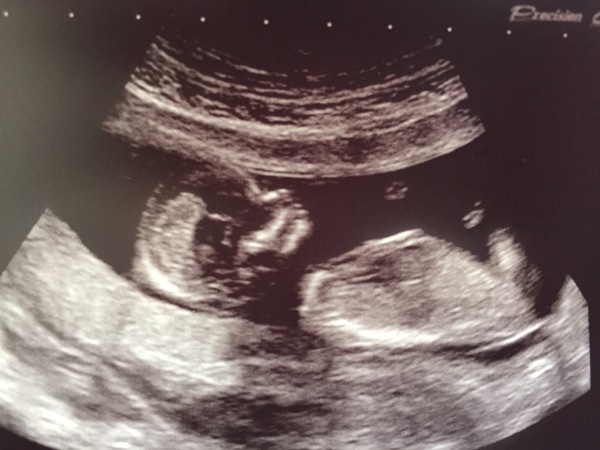

Scan went well and I'm further ahead than I thought. Now 13+1 rather than 12+3 and due on the 9th!

Lovely scan pic friendly. I was further ahead too :) Don't they look so cute all snuggled!